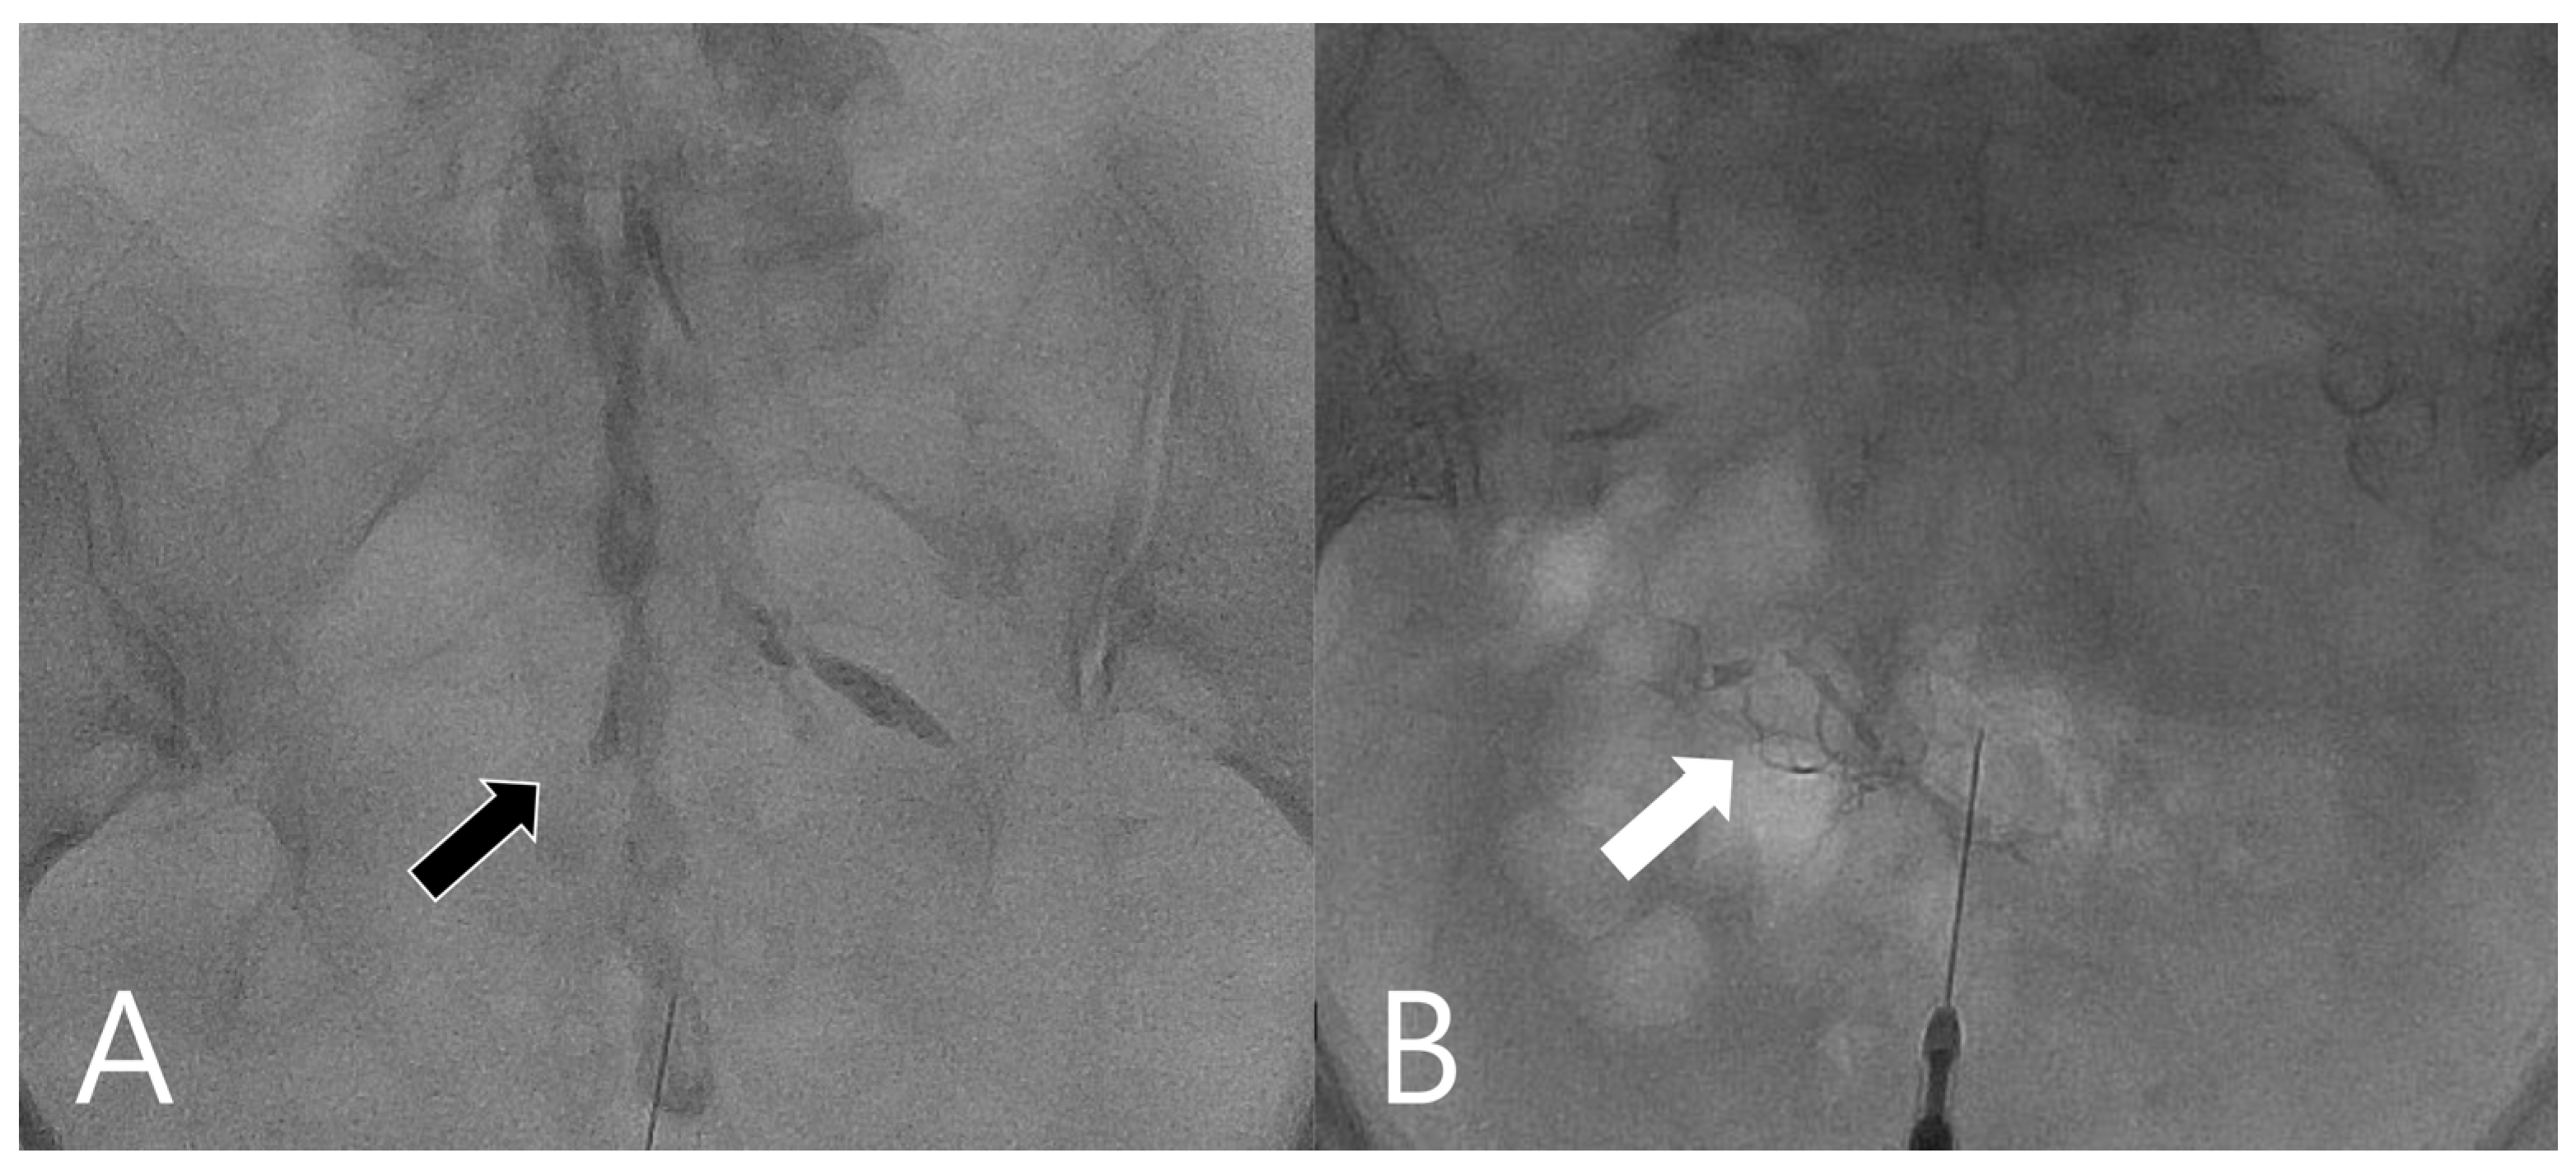

2.2. Procedures